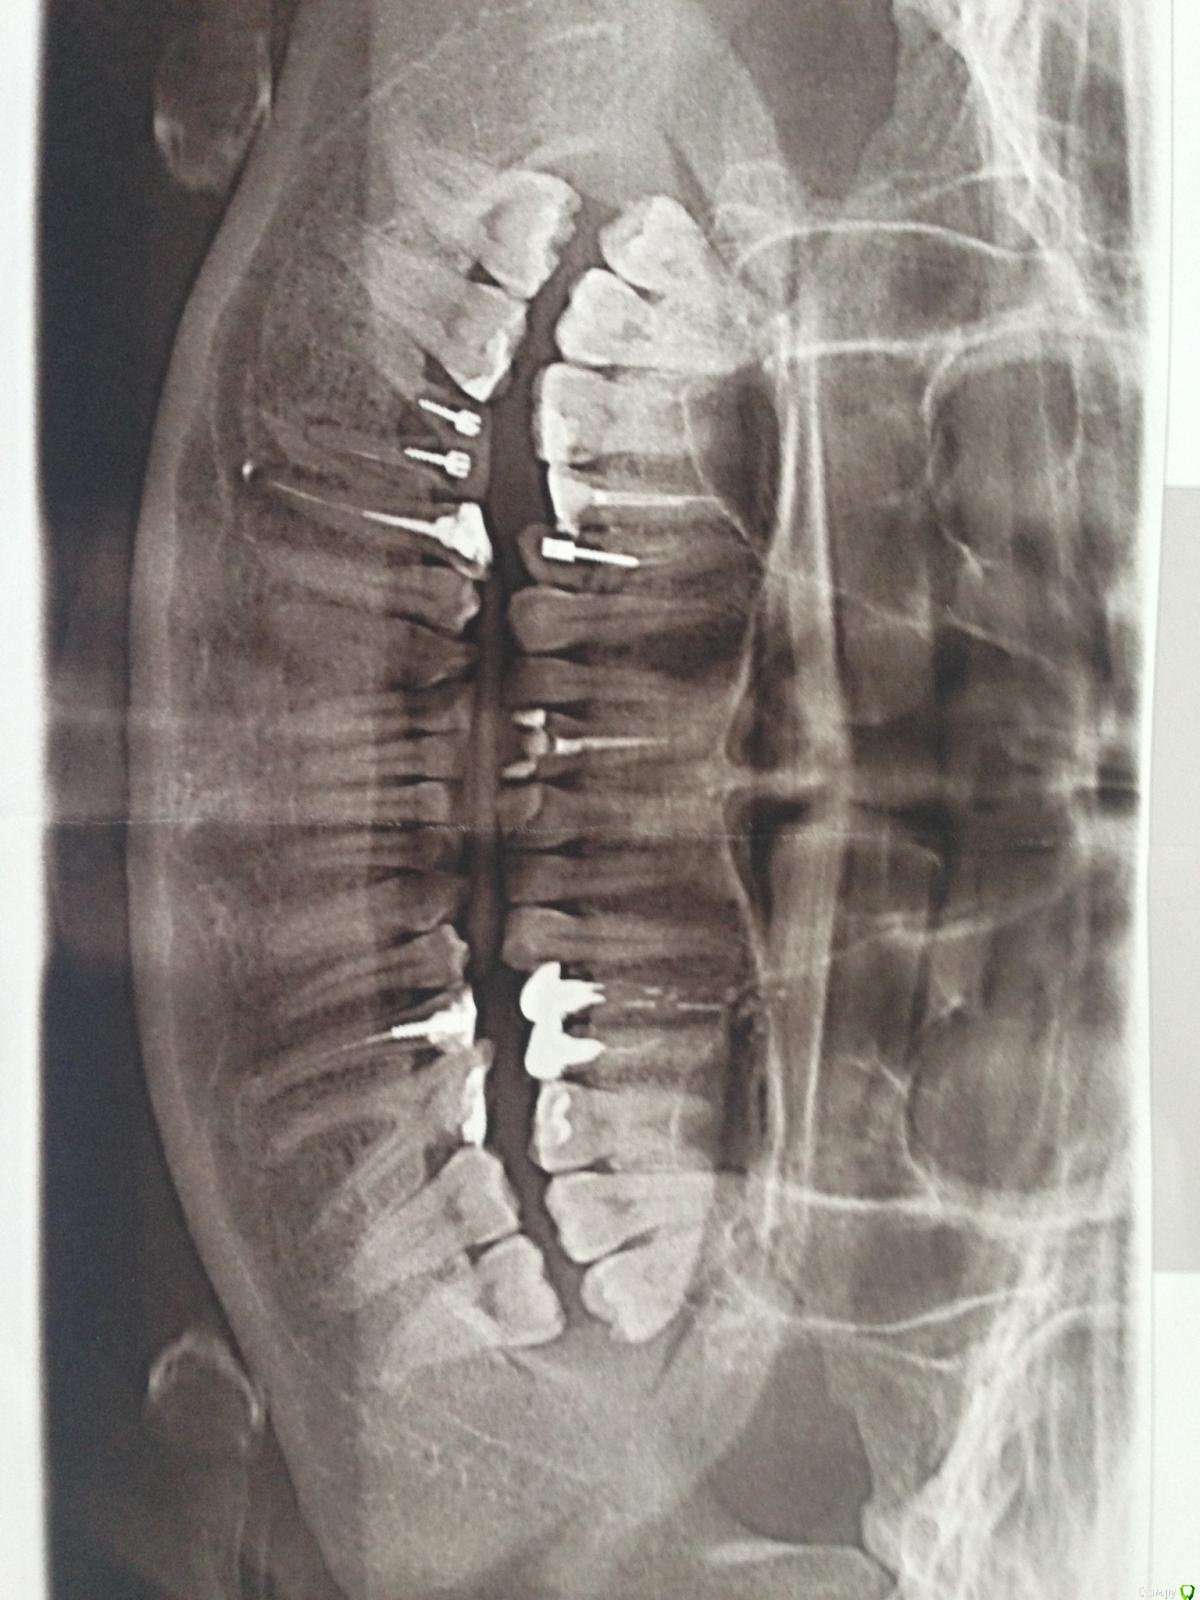

Irina231280 Опубликовано 3 марта, 2017 Поделиться Опубликовано 3 марта, 2017 (изменено) Добрый день! Стоит вопрос об установке имплантолов на места зубов 14 и 46. В 14 после удалёния штифта стоматолог сказал, что ткани очень мягкие и протезировать нельзя. Действительно ли эти 2 зуба только под удаление? И как быть потом с имплантацией? Нужно их удалить и ждать месяц-два или можно делать немедленную имплантацию? Спасибо. Изменено 3 марта, 2017 пользователем Irina231280 Ссылка на комментарий

Doc Опубликовано 3 марта, 2017 Поделиться Опубликовано 3 марта, 2017 Тут гораздо больше двух зубов, подходящих под вопрос, но эти два скорее всего на выход. Ссылка на комментарий

Doc Опубликовано 3 марта, 2017 Поделиться Опубликовано 3 марта, 2017 А какие ещё? И удалять ли эти 2 сейчас и ждать пару месяцев или сразу удаление-имплантация?Это вопросы к лечащему врачу. И отвечать он будет, скорее всего, не по плохой ортопантомограмме, а по хорошей компьютерной томограмме. Ссылка на комментарий